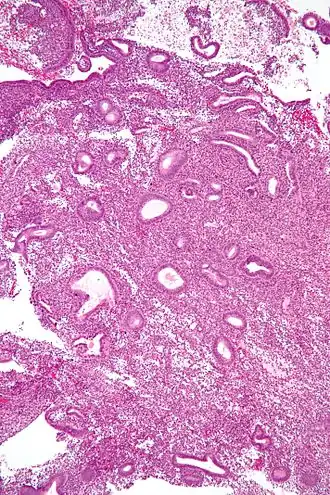

Micrograph showing an endometrial biopsy with simple endometrial hyperplasia, where the gland-to-stroma ratio is preserved but the glands have an irregular shape and/or are dilated. H&E stain.